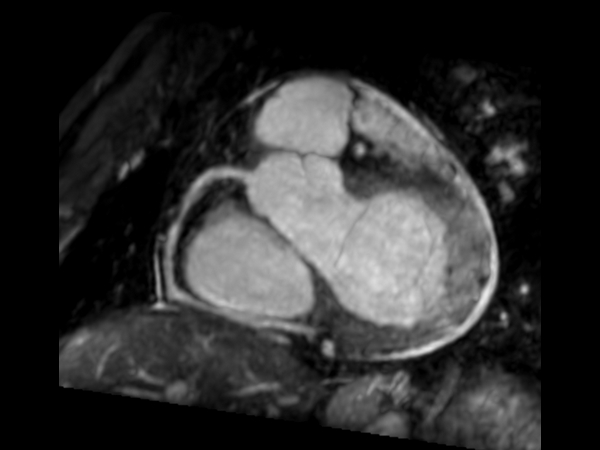

Cine - Short axis